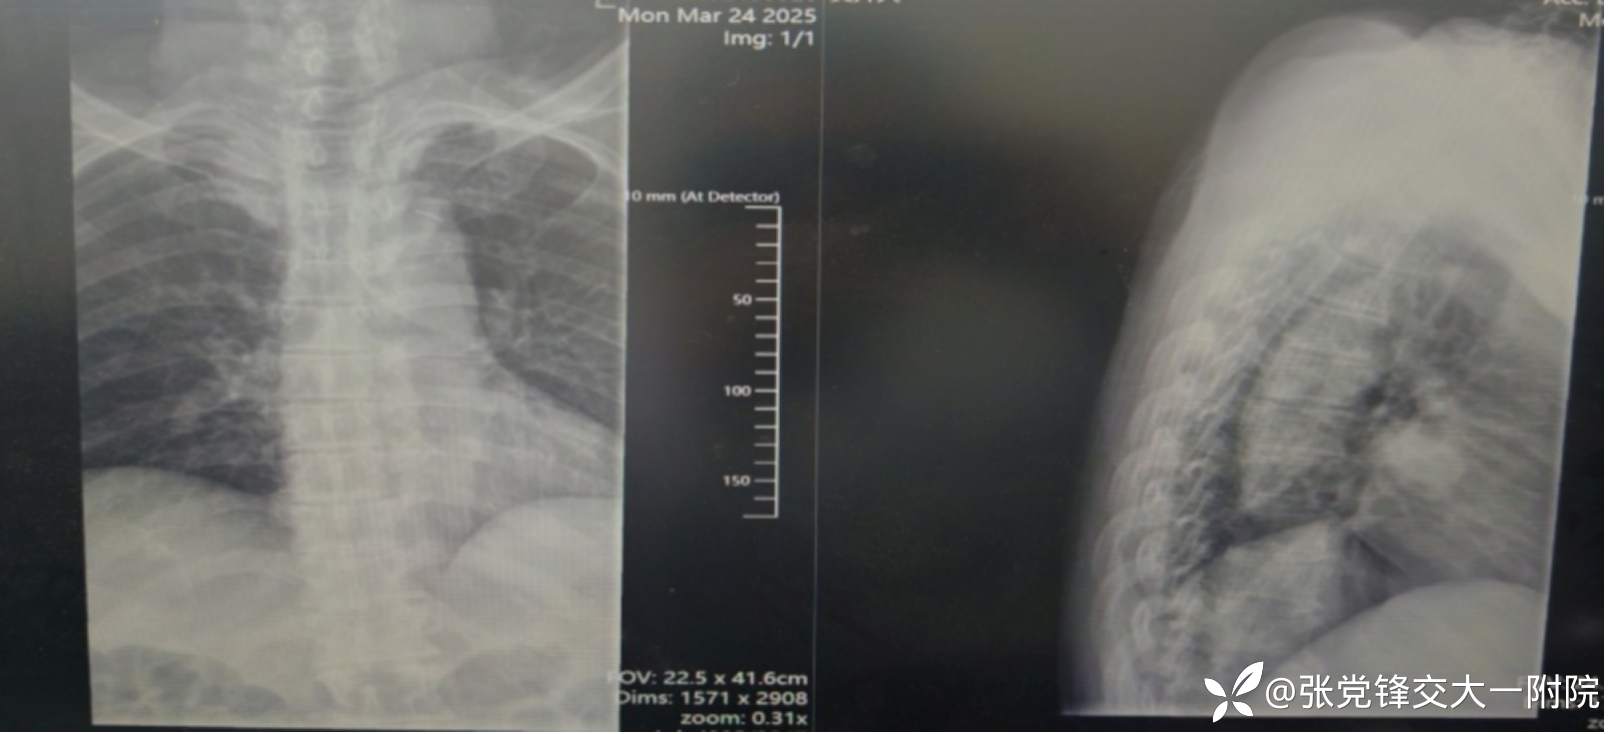

【影像学检查】

术前CT

术前x线片

全身骨显像:胸2-3椎体骨代谢增高,结合病史考虑脊柱结核可能。

1.胸椎结核并不全瘫;2.胸椎管狭窄并脊髓损伤;3.高血压;4.2型糖尿病